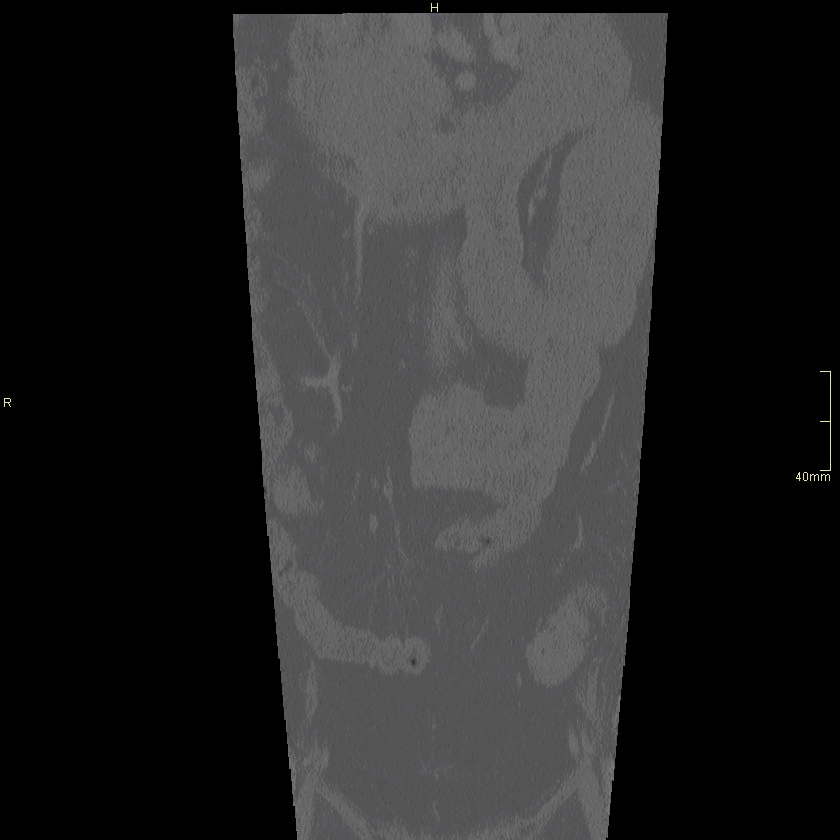

CT Lumbosacral Spine Contrast- Soft tissue window (sagittal)